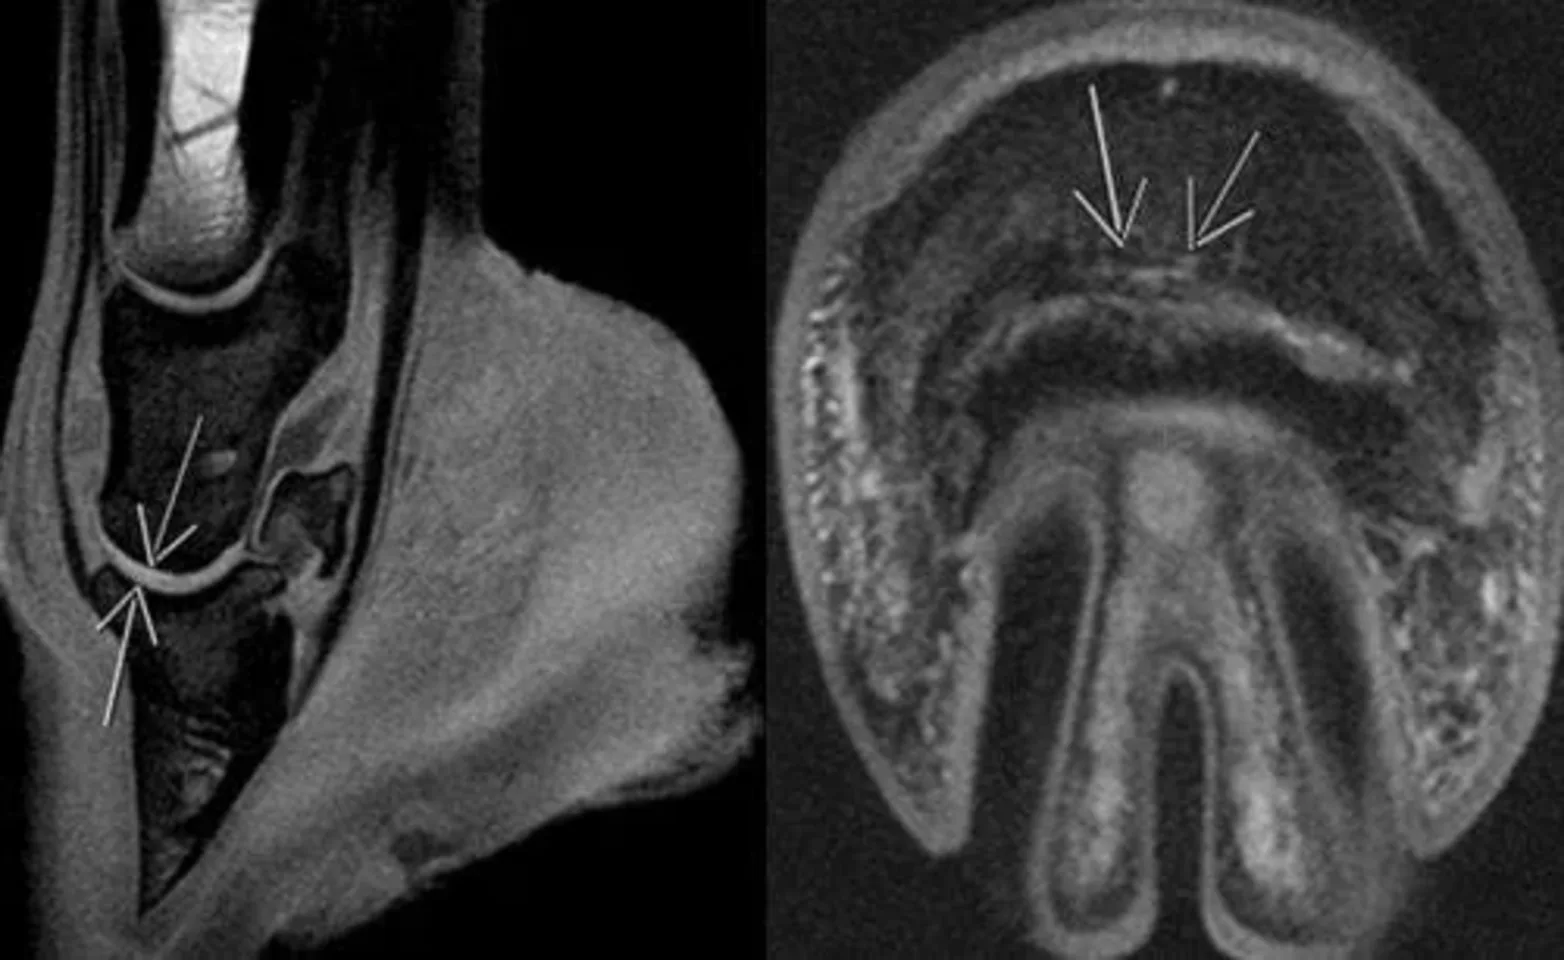

MRI: 1.5 Tesla Siemens Symphony MR unit available for equine and small animal cases

Diagnostic imaging at Oakridge Equine Hospital plays a pivotal role in the accurate assessment and management of equine health conditions, offering invaluable insights into the anatomy and pathology of horses. Utilizing a range of modalities such as radiography (X-rays), ultrasonography, magnetic resonance imaging (MRI), and endoscopy, our veterinarians can non-invasively visualize internal structures and detect abnormalities with remarkable detail and precision. Whether investigating lameness, evaluating soft tissue injuries, or diagnosing skeletal disorders, these imaging techniques enable thorough examination of the musculoskeletal, respiratory, gastrointestinal, and cardiovascular systems in horses. With advancements in technology and expertise, equine diagnostic imaging has revolutionized equine medicine, facilitating timely and accurate diagnoses, guiding treatment decisions, and ultimately enhancing the quality of care and outcomes for equine patients.